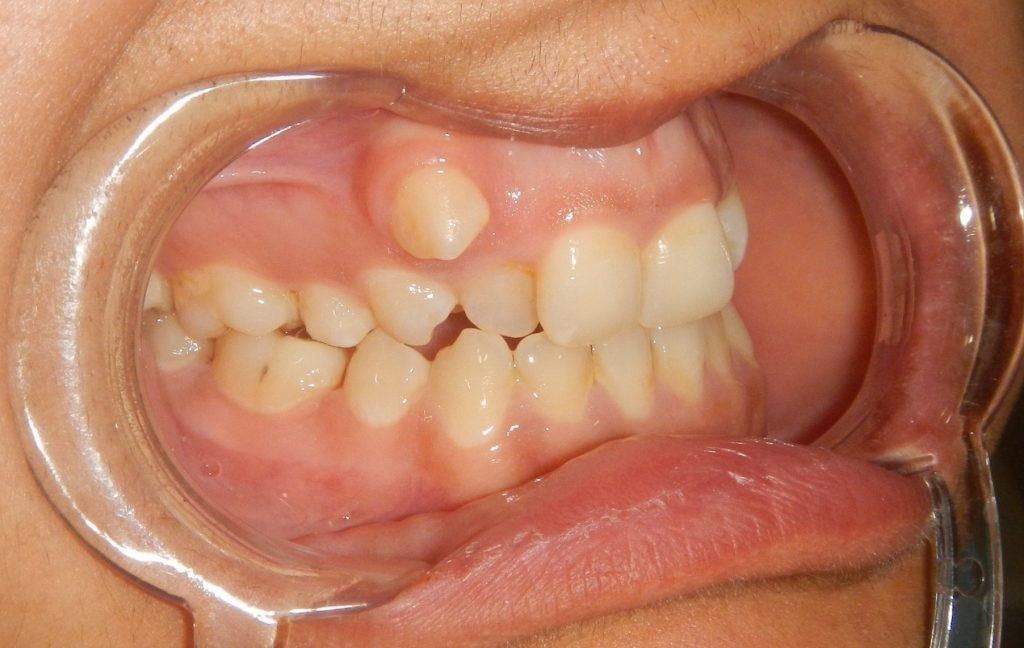

Ukšten zagriz, obrnut zagriz u ranoj mješovitoj denticiji

Nicanje gornjih stalnih zuba iza donjih se stručno naziva “ukršteni zagrižaj”(Slika 3.) i ako se na vrijeme otkrije (prije nego što gornji zubi u potpunosti izniknu i postave se iza donjih), sa jednostavnim vježbama može da se spriječi kasnije nošenje apartata za ispravljanje zuba. Potrebno je da se dijete dovede kod dječijeg stomatologa na pregled. Nakon detaljnog pregleda i procjene same nepravilnost dječiji sstomatolog predlaže mjere interceptivne ortodoncije.

Slika 3. Obrnuti položaj gornjeg desnog sjekutića